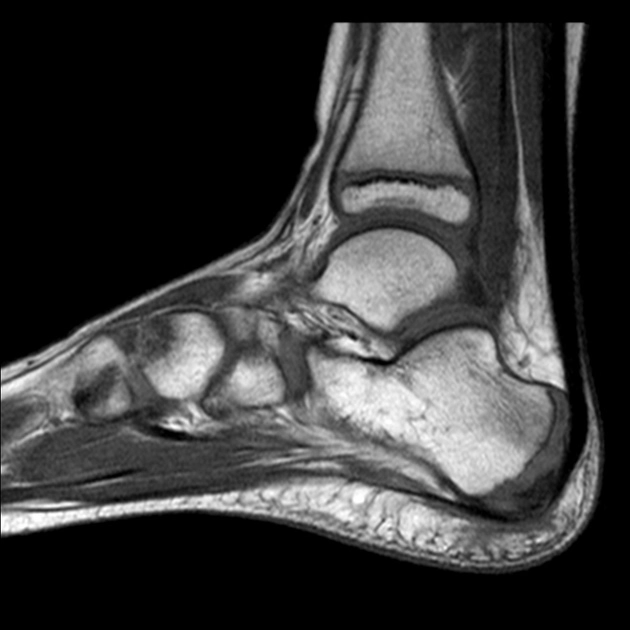

Right heel MRI scans can detect plantar rips or ruptures, tendon injuries, lesions, cysts, and, in some cases, Right heel fractures or spurs.

An MRI Right Heel can also be performed to investigate plantar heel pain and determine what is wrong with your Heel and ankle. It can also be used to make the following diagnoses:

MRI (Magnetic Resonance Imaging) screening of the Right Heel is a non-invasive radiology test used to evaluate the condition of the Right Heel and surrounding tissue. MRI Right Heel is done to look for Right Heel conditions and the surrounding area.